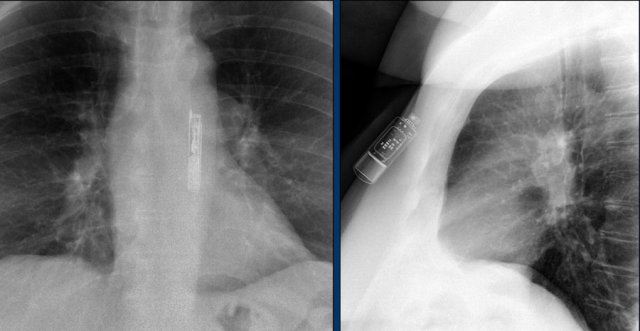

Wiireless pacemaker device

A Micra device is a small wireless pacemaker device, that is transfemorally implanted in the apex of the right ventricle.

Close up view of the Micra device.